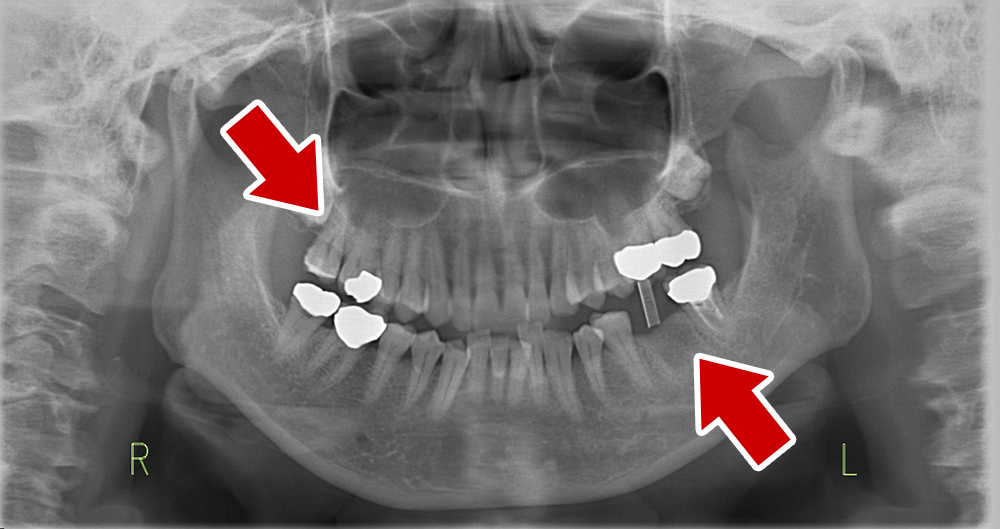

64歳 女性 紹介患者様

- 主訴

- 上下左右の歯が無くて、食べずらい、右下の歯が痛い

- 処置内容

- 右上3本、左上1本、右下3本、左下3本、鎮静麻酔

- 治療費用

- 上顎:約180万円(税込)下顎:約170万円(税込)

- 治療期間

- 上顎:約9か月、下顎:約6か月

- リスク

-

術後の腫れ、痛み(ピークは3日後、1週間で軽減)

上部構造物、仮歯の破折、人工歯根脱落リスクがあります